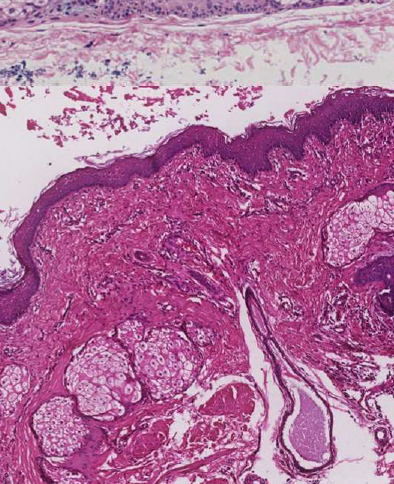

發炎型

| Periapical(radicular) cysts | Rest of Malassez 被刺激 | - | - | true/ periapical cyst 圓形的光通性包圍根尖 |

牙根吸收, 2cm ↑ 根管治療無效  |

- Rest of Malassez

- Hertwig’s epithelial 殘留

- Rushton bodies

- 齒源系上皮